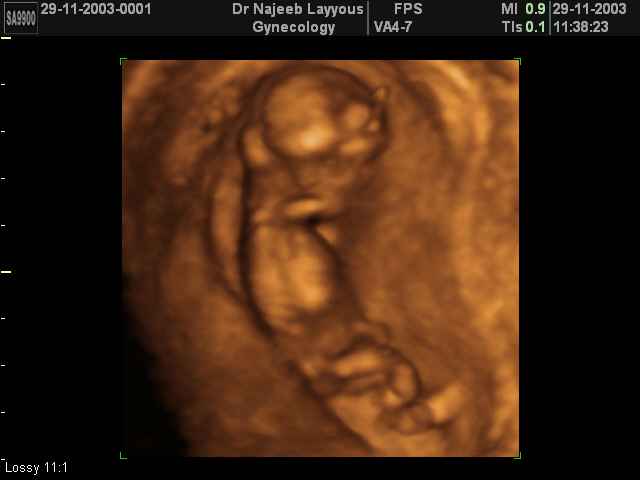

- First Trimester Ultrasound Photos

3D First Trimester Ultrasound Scan Photos ( Early Pregnancy Ultrasound Photos ) | Dr N Layyous